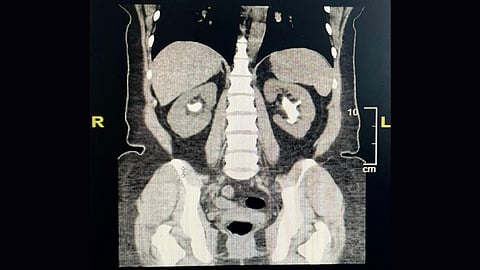

قالت مديرية الشؤون الصحية بمحافظة الطائف، إن أطباء مجمع الملك فيصل الطبي، أنهوا معاناة مريضة كانت تعاني من الحصوات المتشعبة بالكلى.

وأوضحت صحة الطائف –عبر حسابها بموقع تويتر- أنه في عملية تعتبر من العمليات المعقدة، نجح أطباء مجمع الملك فيصل الطبي، من إنهاء معاناة مريضة أربعينية مع الحصوات المتشعبة بالكلى.